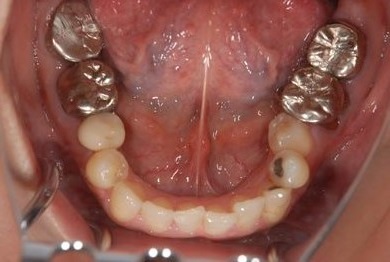

| 性別/年齢 | 女性 / 38歳 | ||||||||||||||||||||||||||||||||

| 主訴 | 奥歯の痛み(虫歯)。銀歯の所だと思います。なるべく痛くない治療がいいです。 | ||||||||||||||||||||||||||||||||

| 治療方針 | セラミック治療にて、審美的回復を行う。 | ||||||||||||||||||||||||||||||||

| 治療内容 | ハイブリッドセラミッククラウン1本(ハイブリッドセラミック用土台1本) | ||||||||||||||||||||||||||||||||

| 総治療費 | 96,600円 | ||||||||||||||||||||||||||||||||

| 治療期間 | 2ヶ月 |